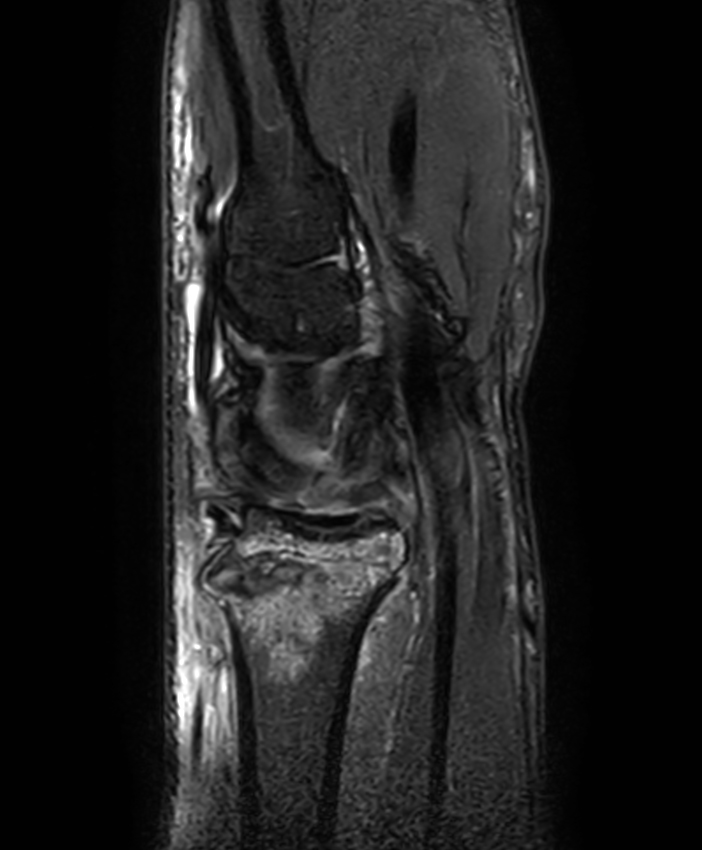

Patient with a wrist fracture. Compressed SENSE is used in all sequences, reducing the scan time while maintain equal image quality compared to scans without Compressed SENSE. 3D sequences have been added to this ExamCard with a comparable in-plane resolution but much thinner slices. Due to the shorter scan times that can be achieved thanks to Compressed SENSE, these 3D sequences could potentially replace the 2D sequences providing more confidence in making the diagnosis.

2D Sagittal PDw SPAIR

3D Sagittal PDw SPAIR